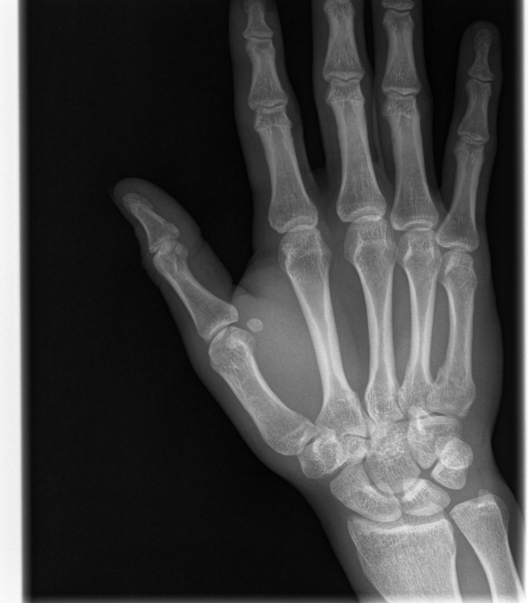

Broken Hand

This was just a hairline fracture that I managed to get from a soccer game. I thought it was pretty cool that I was given all of the digital copies.

A black and white x-Ray image of a persons right hand.